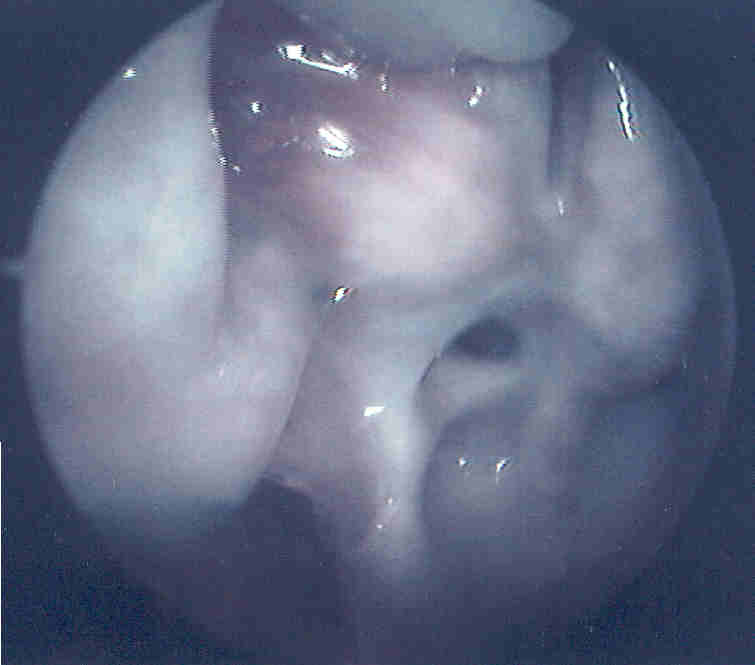

The patient in thes two pictures had recurrent sinus difficulties following sinus surgery.  He described thick mucus (behind uncinate remnant above) expelled from his nose which brought temporary relief, but the problem would recur.  At surgery he was found to have a complete ring of thickened mucus travelling between his natural and iatrogenic/accesory ostia.  Below: a suction tip is just visible inferiorly pulling on some tenacious, translucent nasal mucus.  The ostia were connected to eliminate this "recirculation ring" effect.